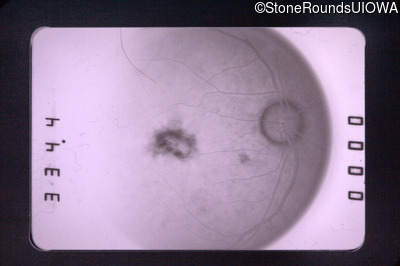

Fluorescein Angiography - Left - 20/400

Exemplar